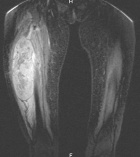

66 year old woman c/o right thigh pain x11 weeks, 20 lb weight loss in 5 weeks

Zoom image: Cell stain Cell stain.